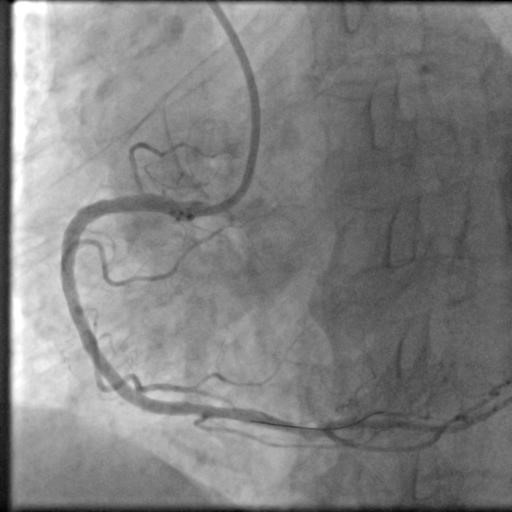

17时30分,陈奶奶已躺在导管室的手术台上,副主任医师朱劲草与王东一起为她进行血管造影。高清的影像图令所有人都禁不住倒吸一口冷气——右冠脉近中段起全部闭塞,仅可见75px左右血管,左冠前降支回旋支也有多处重度病变!

“赶紧开通右冠放支架。”在朱劲草冷静果断的判断下,心内团队成员各就各位,迅速开始了相应处理。

从进入导管室到所有操作结束,整台手术仅花费了不足一小时,然而这看似波澜不惊实则危机涌动的几十分钟,挽救了陈奶奶的性命。

“老人胸闷不适其实好多天了,但是自己并不重视,来医院的时候也说不清症状,我们很难精确判断心梗发作的具体时间与程度,但根据术后影像显示,老人来医院时已经比较危险了,如果家属没能意识到严重性,再多耽误一会儿,可能回天乏术了。”术后,朱劲草认真解释道。